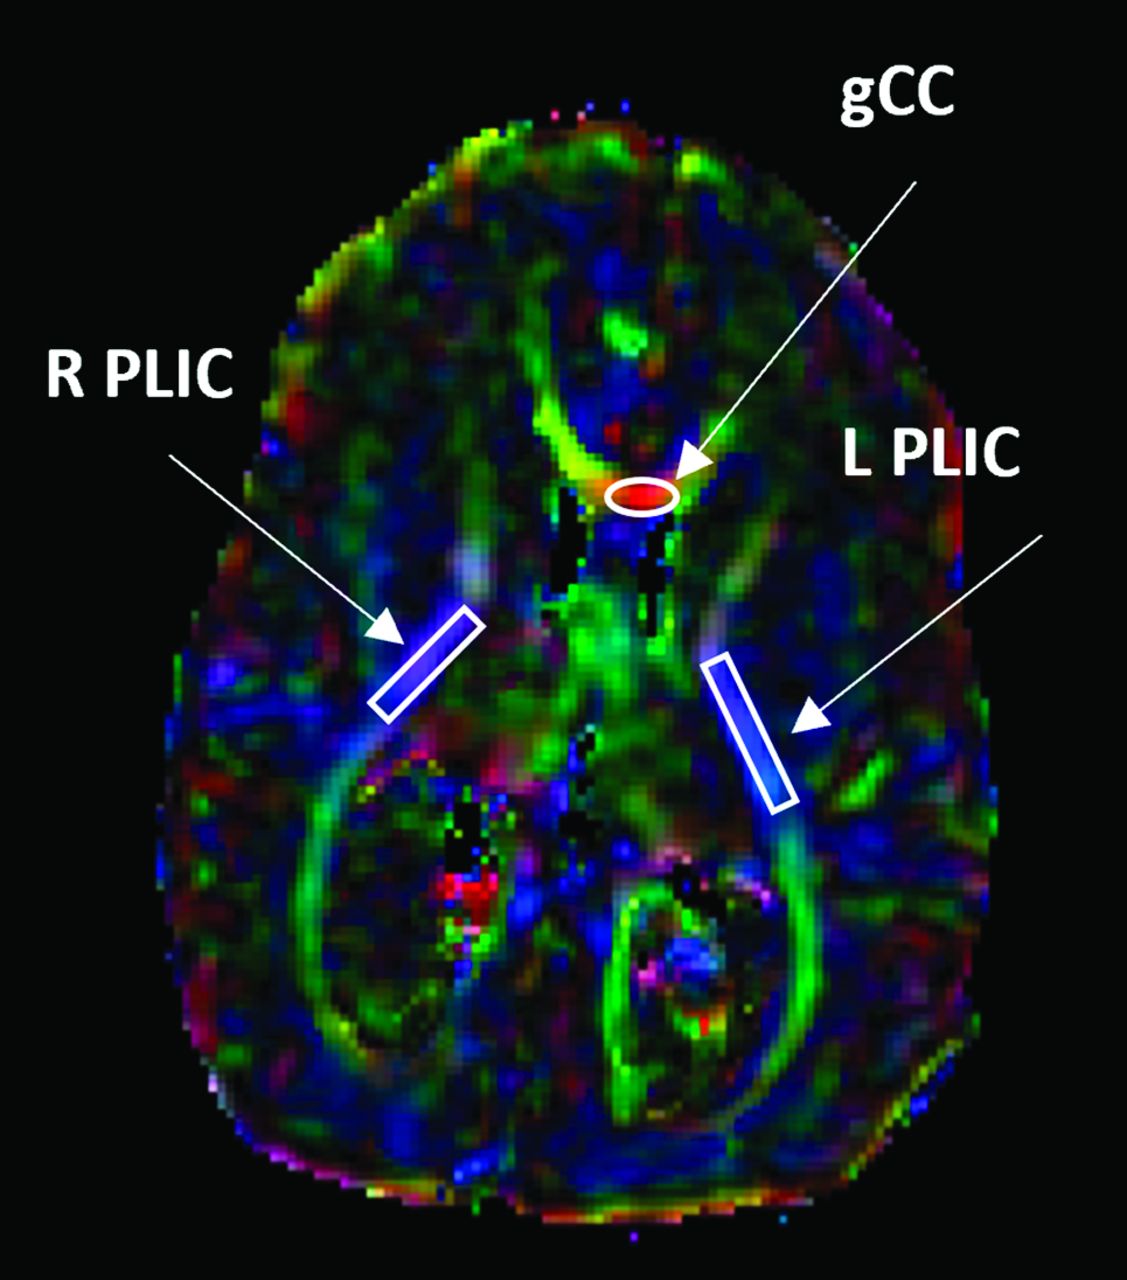

DTI data were acquired with a 15-direction spin-echo EPI sequence on a 1.5T Optima MR430s scanner (GE Healthcare) customized for infant scanning.18-20 Additional sequence specifications included the following: TR/TE = 10,000/93–98.1 ms; FOV = 200 × 200 mm; acquisition matrix = 128 × 28; in-plane resolution (resampled) = 0.78 × 0.78 mm; section thickness = 3 mm; 30 or 32 slices; b-value = all 800 with 1 exception of 1000 s/mm2; 1 B0; 1 average. All DTI data underwent preprocessing and analysis using the DTIStudio software (Johns Hopkins University). Additional details of the infant MR imaging scanner and the imaging sequence specifications have been reported elsewhere.4,18-20 The neuroimaging variables derived from DTI measures included fractional anisotropy (FA) and mean diffusivity (MD) in 2 WM regions (Fig 1): the genu of the corpus callosum (gCC) and the posterior limb of the internal capsule (PLIC). On the basis of our previous data as well as reports in the literature, DTI values in these 2 ROIs were often found to be abnormal in pediatric patients with hydrocephalus or myelomeningocele.5,13,21-25 The fronto-occipital horn ratio (FOHR),26 based on MR imaging acquired at the time of DTI scan, was also included in the model to account for the potential effect of the severity of ventriculomegaly. Sex was tested for its significance in affecting the predictive value of the composite index. Two timing variables, including the gestational age at which the postnatal DTI data were acquired and the gestational age at which the MOMS criteria for shunt placement were assessed, were included as potential confounders in the model.

Illustration of ROI delineation in WM in children with prenatal MMC repair on a color-coded FA map. Arrows denote areas of the gCC, L PLIC, and R PLIC. L PLIC indicates left posterior limb of the internal capsule; R PLIC, right posterior limb of the internal capsule.